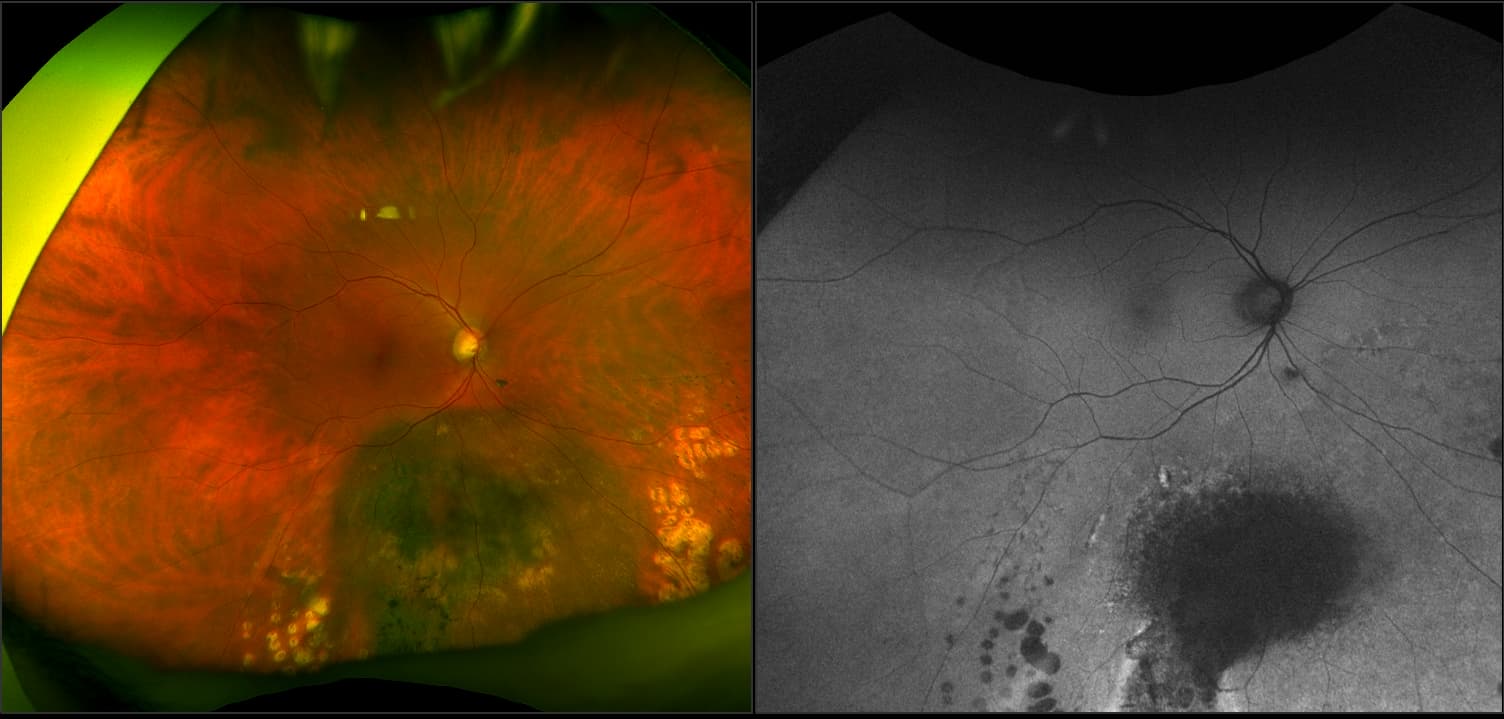

California - Choroidal Nevus, RG, AF

A choroidal nevus is simply an accumulation of melanocytes in the choroid. They are a space occupying mass or a benign melanoma. Choroidal nevi are slate gray in color, have indistinct margins, and may be slightly elevated (1-2 diopters). Since they are in the choroid, they are usually only seen in the red separation and not the green. The green separation may show the RPE degeneration associated with nevi which is seen as pigment mottling and drusen.